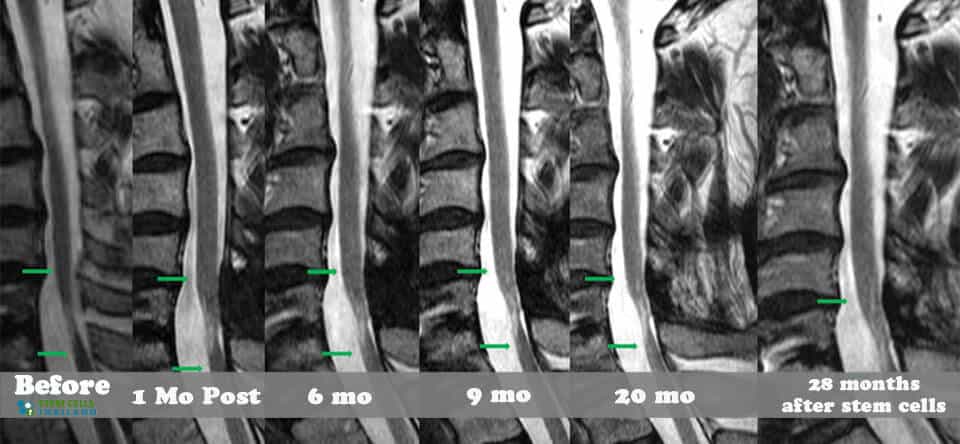

組織、軟骨或韌帶的新?lián)p傷對(duì)干細(xì)胞治療的反應(yīng)要好得多。治療后的康復(fù)需要大量的奉獻(xiàn)和康復(fù)訓(xùn)練。初次治療后約2-3個(gè)月,身體改善明顯,且效果是永久性的。[2]

- 早期階段(6個(gè)月至2歲)損傷通常會(huì)比傳統(tǒng)上對(duì)兩歲以上損傷反應(yīng)良好的效果好得多。[3]